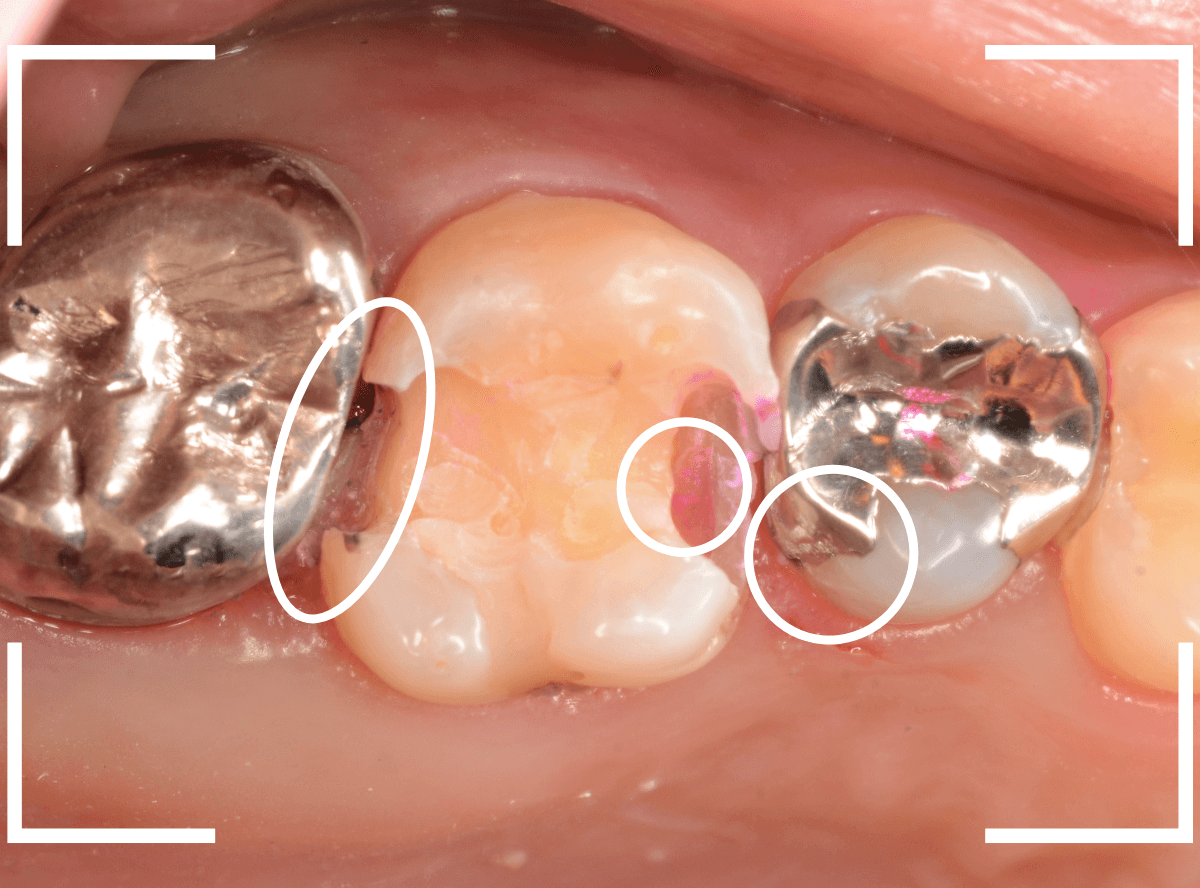

Case.18 虫歯なのは間違いないが、境界がはっきりしない

「つめものが外れて、噛むと痛い」という訴えで来院された患者さんさんです。

一見で、表面が虫歯になっているのと、レジンが劣化しているのがわかります。

レントゲン写真で確認します。

〇部が当該の歯です。

症状もあるので、虫歯が深そうですが、全体がもやっとして、どこからどこまで虫歯なのかはっきりわかりません。

まれに、こんな時もあります。

レジンを外し、虫歯の処置を進めます。

慎重に虫歯を除去し、一安心か、という寸前で(〇部、小さく出血しているところ)露髄してきました。

神経を除去しないとダメかもしれません。。。

神経を保護するお薬をつめて、経過観察します。

痛みが出ませんように。。。